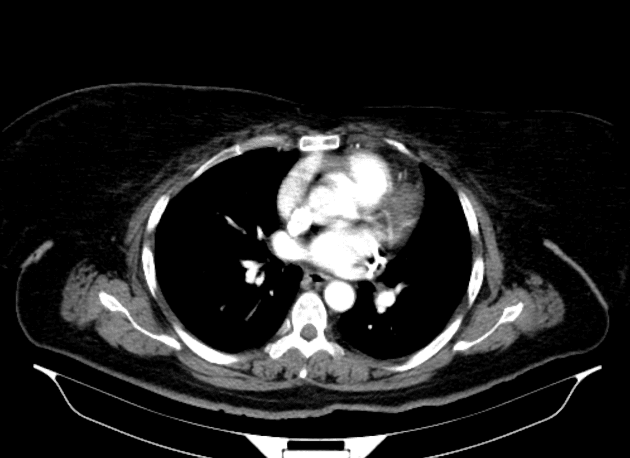

- Thấy một tổn thương tăng tín hiệu trên T1, giảm tín hiệu trên T2 (T1 hyperintense, T2 hypointense), khu trú tại thùy đuôi gan, có hạn chế khuếch tán ở vùng trung tâm (central restricted diffusion) và không có tăng quang đáng kể sau tiêm thuốc cản quang (no significant post-contrast enhancement).

- Không thấy mỡ trên hình ảnh out-of-phase (no fat on out-of-phase images).

- Các tĩnh mạch cửa và tĩnh mạch gan thông thương tốt (patent portal and hepatic veins).

- Không có giãn đường mật trong gan hoặc ngoài gan (no intra or extrahepatic biliary dilatation).

- Hình ảnh học phù hợp nhất với u tuyến gan có xuất huyết vào trong tổn thương (imaging features are most consistent with a hepatic adenoma with hemorrhage into it).

- "Xuất huyết trong tổn thương u tuyến gan có thể biểu hiện tăng tín hiệu trên T1, giảm tín hiệu trên T2 và hạn chế khuếch tán."

Xuất huyết vào u tuyến gan là một biến chứng nghiêm trọng tiềm tàng của khối u gan lành tính, thường liên quan đến việc sử dụng thuốc tránh thai đường uống kéo dài. Hình ảnh học thường cho thấy tổn thương tăng tín hiệu trên T1, giảm tín hiệu trên T2 do methemoglobin trong xuất huyết bán cấp, với mức độ tăng quang thay đổi. Việc không thấy mỡ trên hình ảnh out-of-phase và không tăng quang đáng kể giúp phân biệt với các khối ác tính như ung thư biểu mô tế bào gan. Việc xác định chẩn đoán cần kết hợp lâm sàng, đặc biệt là tiền sử sử dụng hormone. Quản lý có thể bao gồm ngưng thuốc tránh thai, theo dõi định kỳ hoặc cắt bỏ ngoại khoa tùy theo kích thước, triệu chứng và nguy cơ vỡ.